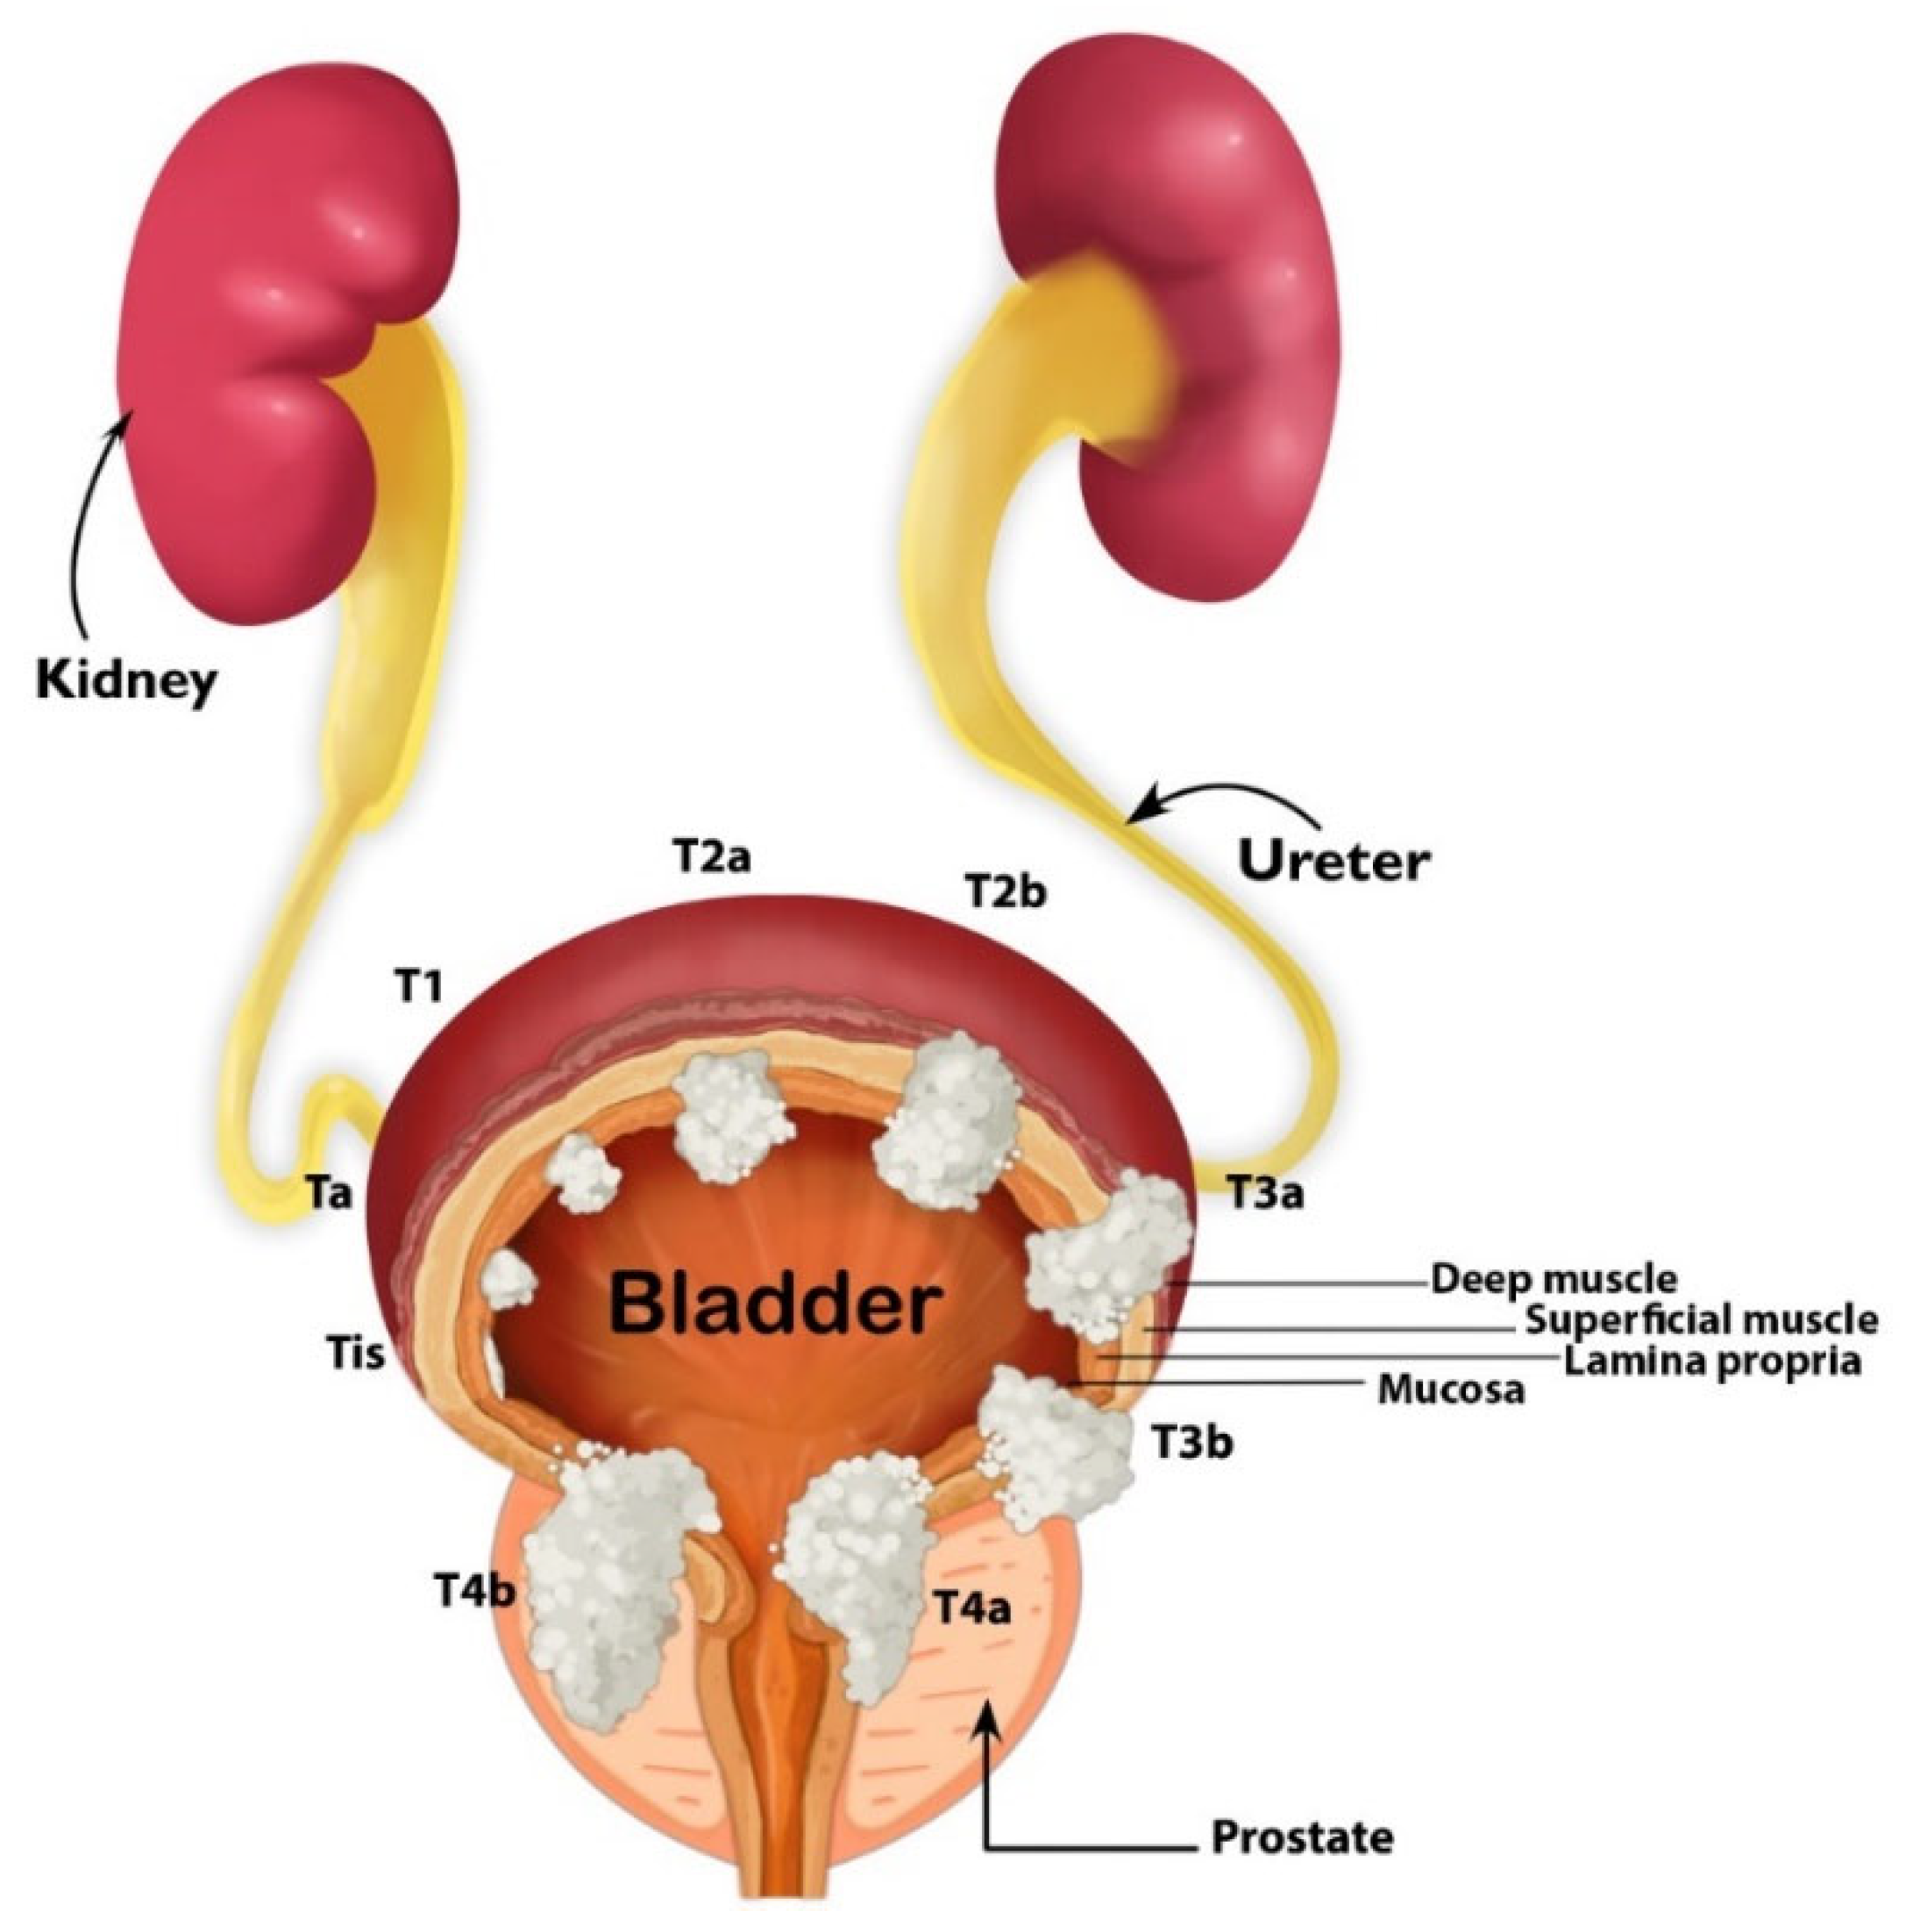

Illustration of different pathological stages of bladder cancer. Stage …

Classification Of Bladder Tumors : TNM stage classification of bladder …

Stages of bladder cancer from Meyer et al., (2002). Bladder cancer can …

Overview of staging and grading of bladder cancer tumor. The figure was …

Classification Of Bladder Tumors : TNM stage classification of bladder …

Bladder Cancer Staging | MedicineBTG.com